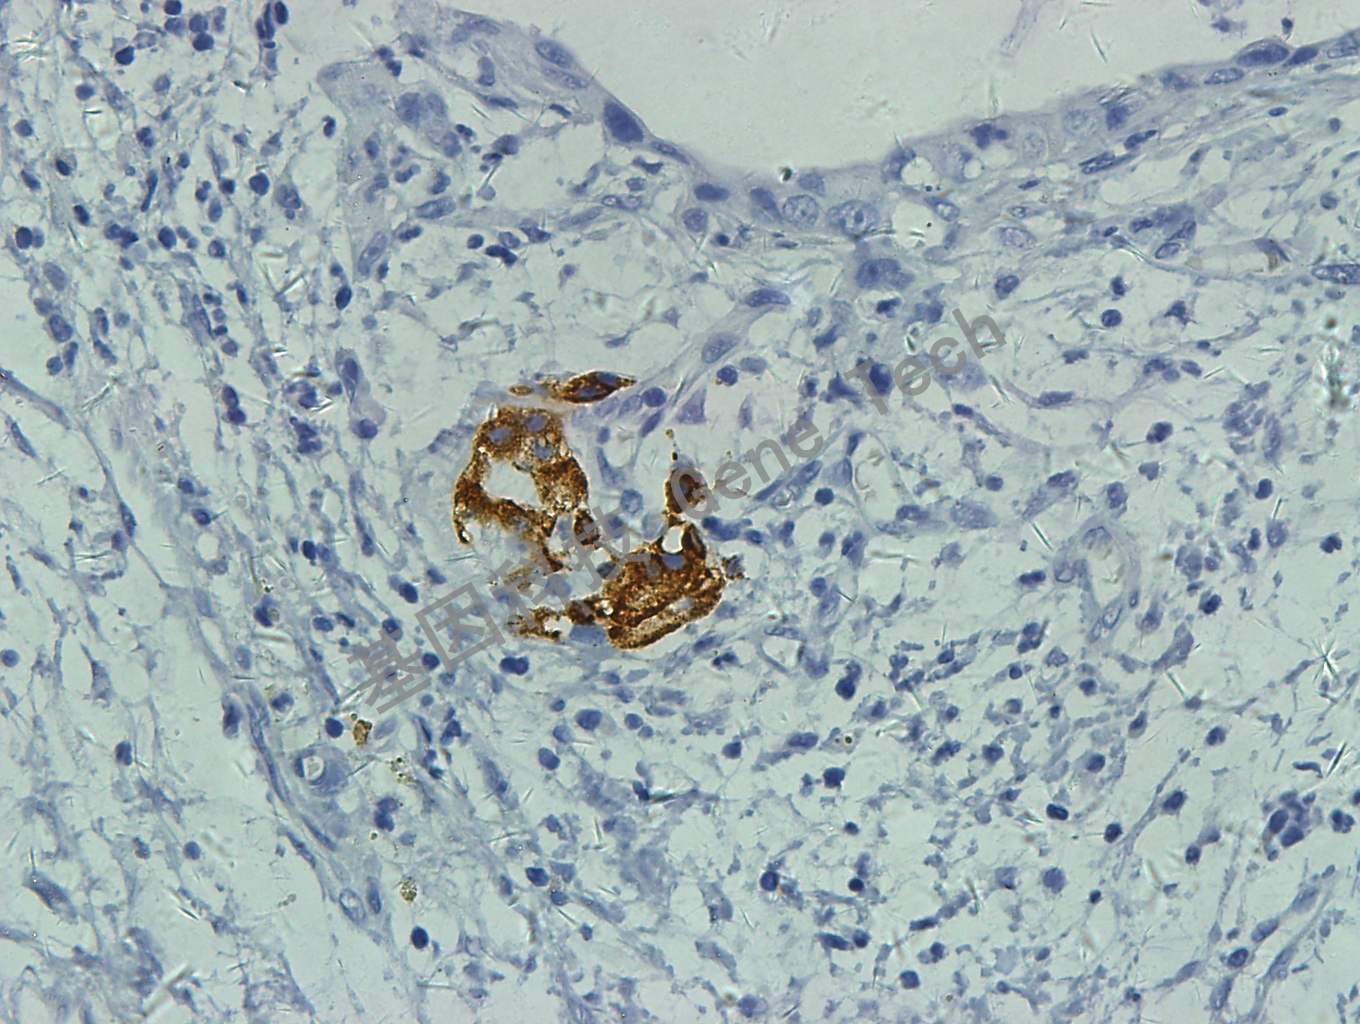

胰腺癌石蜡切片,用 Insulin(GT2131)染色,细胞浆阳性,DAB 显色。

insulin GT2131 胰腺癌1 40X_副本.jpg胰腺癌石蜡切片,用 Insulin(GT2131)染色,细胞浆阳性,DAB 显色。